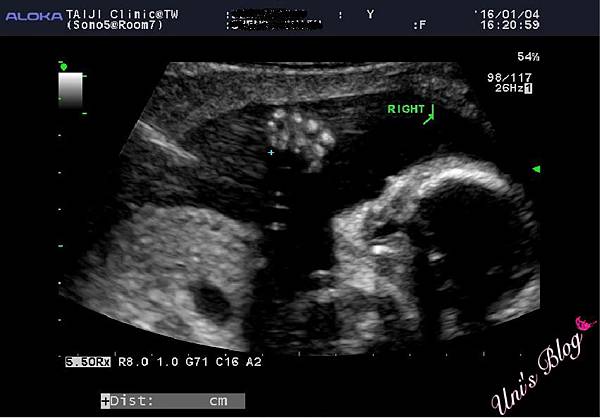

孕媽咪♥22W。高層次超音波-台兒診所